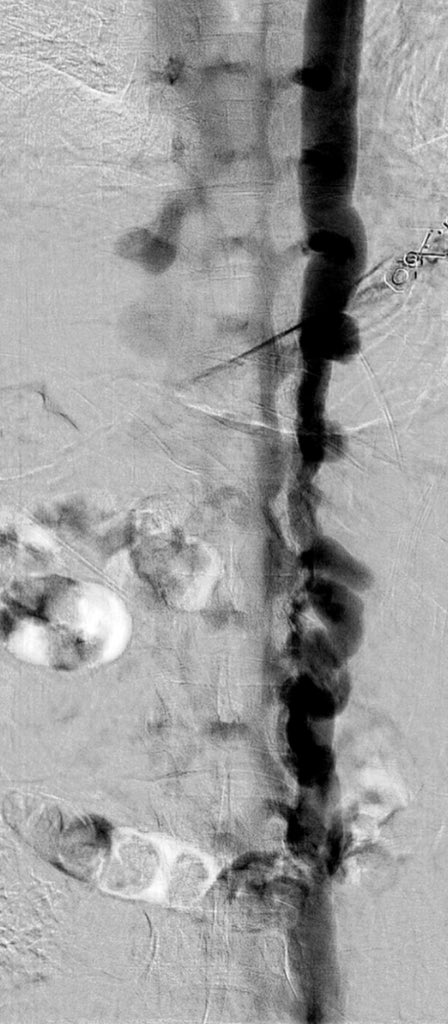

@ChengaziMD @t_intheleadcoat @SDhandMD @drochohan @kmadass @JayMathewsMD @CHICKVIR @Dr_Sudi @DrJayMohan @hkdamonster @SyedYNaqvi1 Nice save with minimal XR, a little IVUS as well? Lucky to have your expertise. I’ve also been preferring IJ when possible